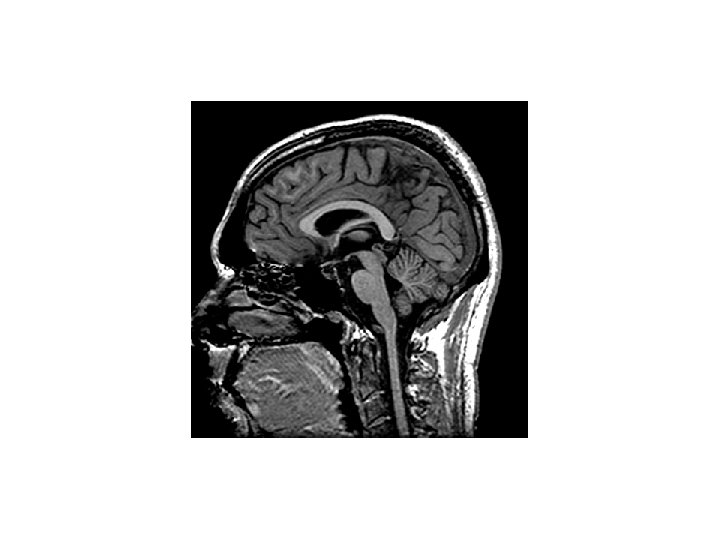

A liquor terek vázlatos rajza a központi idegrendszer median sagittalis metszetén Plexus choroideus